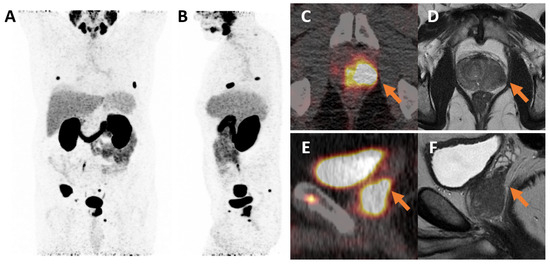

2.2. Imaging Protocol and Evaluation